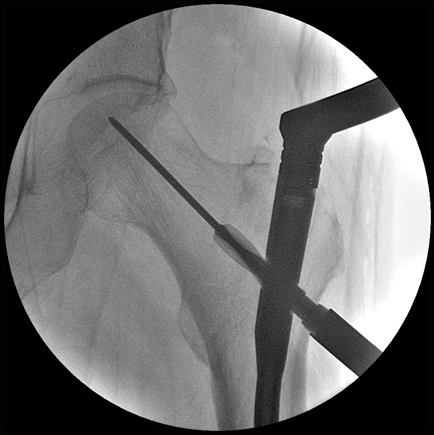

MetalSmart — автоматическое исключение артефактов от металла

Артефакты от имплантатов и других металлических объектов могут скрывать анатомические структуры, затруднять визуализацию и снижать точность диагностики. Программа MetalSmart исключает артефакты от металла, не влияя на контрастность изображений и позволяя избежать увеличения дозы рентгеновского излучения, что происходит при наличии металлических объектов в поле исследования.